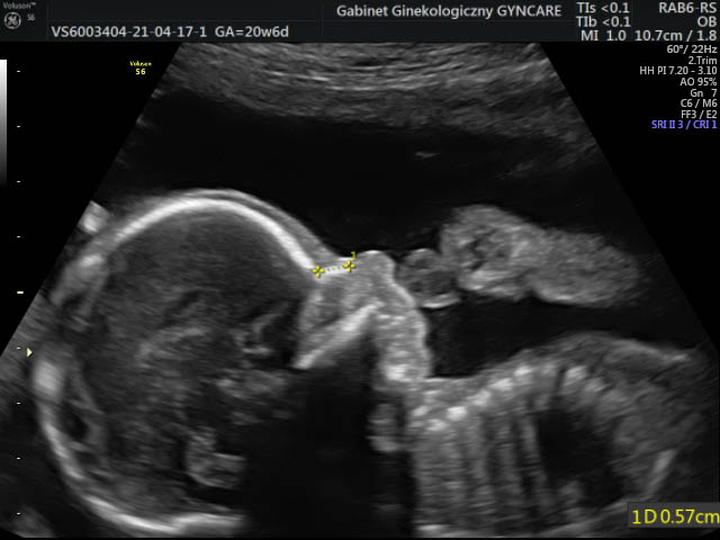

Podczas badania lekarz szczegółowo ocenia anatomię dziecka. Tutaj nie ma miejsca na oszustwa, a średnia waga płodu to nie żadna bajka. Rzeczywisty przegląd obejmuje pomiar obwodu główki, długości kości oraz sprawdzanie stanu kręgosłupa, ponieważ wszelkie wady mogą prowadzić do licznych problemów. Oczywiście lekarz również kontroluje stan narządu rodnego, a rodzice często na tym etapie odkrywają, czy szykują się na kolejne różowe lub niebieskie zakupy. Warto jednak pamiętać, że lekarz nie daje 100% pewności, choć USG połówkowe potrafi wykryć około 90% wad wrodzonych!

- Dokonuje się pomiaru obwodu główki oraz długości kości.

W trakcie USG połówkowego lekarz stanie się archeologiem, odkrywającym tajemnice Twojego dziecka. Zajmie się różnymi pomiarami, takimi jak obwód głowy, długość kości udowej i wiele innych. To pełnowymiarowy przegląd, który pokaże, czy maluszek rozwija się zgodnie z planem. Jeżeli masz ochotę poznać płeć, nie wahaj się domagać od lekarza gorliwego zajęcia się także „sprawami płciowymi” – w końcu każdy rodzic pragnie wiedzieć, czy w przyszłości czeka go męski lub żeński „kolorowy” remont w pokoju!